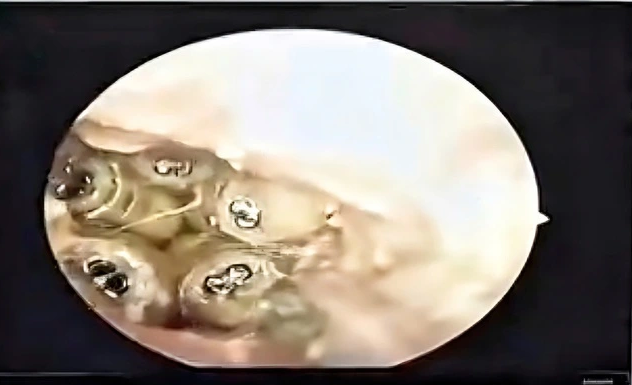

Old  Default Gắp 5 con giòi sống trong tai bệnh nhân

Các bác sĩ Khoa Tai mũi họng, Bệnh viện đa khoa Khánh Hòa vừa gắp 5 con giòi sống trong tai bệnh nhân 48 tuổi.

Trước đó, ngày 23.10, một nữ bệnh nhân 48 tuổi được người nhà đưa đến Bệnh viện đa khoa Khánh Hòa trong tình trạng tai sưng to, chảy dịch và đau dữ dội. Khi tiến hành soi tai, bác sĩ bất ngờ phát hiện nhiều vật thể màu trắng đang ngọ nguậy bên trong ống tai.

5 con giòi sống trong tai bệnh nhân

ẢNH: CẮT TỪ CLIP

Sau khi hút sạch dịch trong ống tai, các bác sĩ đã gắp ra 5 con giòi còn sống cùng xác một con côn trùng nằm sát màng nhĩ. Theo nhận định của bác sĩ, do bệnh nhân không thể tự chăm sóc bản thân, trong quá trình sinh hoạt có thể côn trùng đã chui vào tai, làm tổ và đẻ trứng, sau đó trứng nở thành giòi.

Đại diện Bệnh viện đa khoa Khánh Hòa cho biết, rất may trường hợp này được phát hiện kịp thời, nếu chậm trễ, bệnh nhân có thể bị thủng màng nhĩ, gây tổn thương nghiêm trọng đến thính lực. Đây là lời cảnh báo về việc cần chú trọng chăm sóc, vệ sinh tai mũi họng, đặc biệt với những người không thể tự vệ sinh cá nhân.